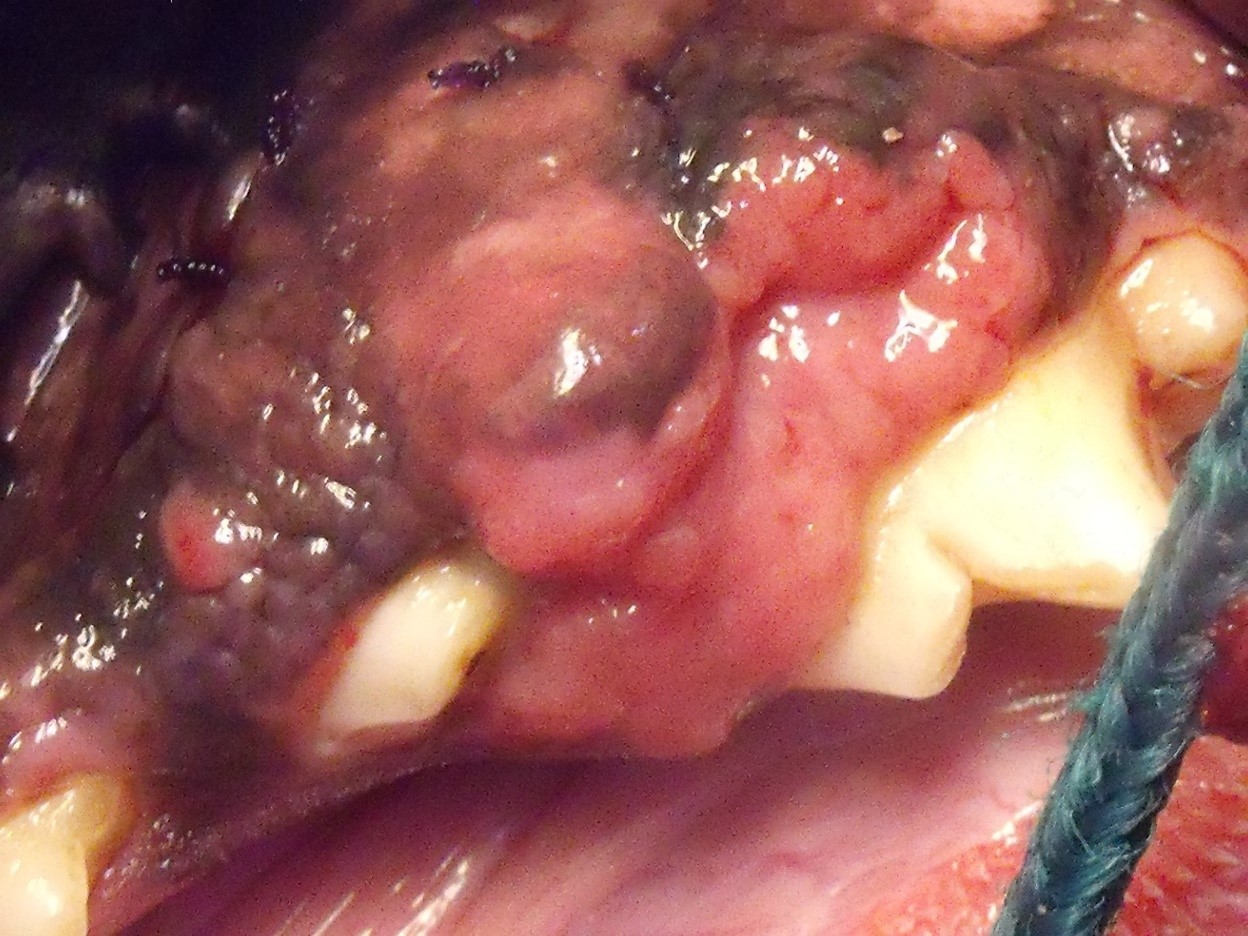

Die Gewebewucherung war dunkel pigmentiert und hatte eine blumenkohlartige Struktur. Mehrere Erkrankungen kamen zunächst in Frage. Als gutartige Wucherung kamen acanthomatöse Ameloblastome und sogenannte Epuliden (Zahnfleischwucherungen) in Frage. Die bösartige Variante sind Melanome, Fibrosarkome oder Plattenepithelkarzinome, um nur ein paar wenige zu nennen. Im Verlauf der weiteren Untersuchung unter Narkose zeigte sich, dass ein Zahn im Bereich der Wucherung lose ware. Der Knochen war ebenfalls betroffen. Der Zahn P4 im Oberkiefer biss in die Masse ein. Dies führte zu den Blutungen und war die Ursache für das Blut im Wassernapf von Mr. President. Beide Zähne, der lose Zahn und der, der in die Masse einbiss, wurden entfernt.

Aus unterschiedlichen Bereichen im Maul wurden Gewebeproben entnommen und zu Untersuchung in die Pathologie geschickt. Wenige Tage später erhielten wir das Ergebnis des Labors. Bei der Wucherung handelte es sich um ein acanthomatöses Ameloblastom, einen gutartigen Tumor, der jedoch wie ein bösartiger Tumor in das Gewebe und den Knochen wächst. Er metastasiert (streut) allerdings nicht. Ameloblasten sind Zellen, die bei der Zahnentwicklung entstehen. Der Zahnschmelz wird aus diesen Zellen gebildet. Die Ameloblasten gehen normalerweise beim Zahndurchbruch verloren. Einige der Zellen können jedoch auch im Zahnhalteapparat verbleiben und beim älteren Hund Tumoren entstehen lassen. Diese Tumoren können an unterschiedlichen Stellen im Kiefer auftreten, meistens jedoch im Unterkiefer im Schneidezahnbe reich. Es kann jedoch jeder andere Zahn betroffen sein. Bei Mr. President hat sich der Tumor im Seitenzahnbereich des Unterkiefers gebildet.

Die Besitzerin des Patienten legte viel Wert auf die Erhaltung von möglichst viel gesundem Gewebe. Der vordere Bereich mit Eckzahn und Schneidezähnen, zwei Backenzähne und das Kiefergelenk sollten geschont werden. Es wurde eine Teilresektion des Unterkiefers vorgenommen. Das betroffene Gewebe wurde entfernt und in die Pathologie geschickt. Der Befund zeigte, dass sich die Operationsgrenzen im gesunden Gewebe befanden.